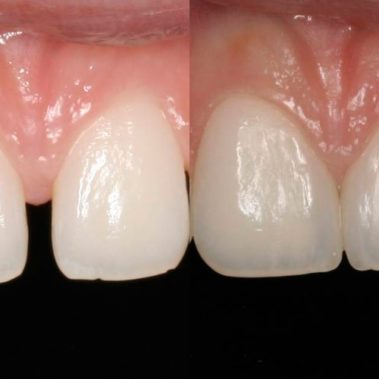

Unser hochqualifiziertes Praxisteam aus Zahnärzten und Mitarbeiterinnen steht Ihnen mit Achtsamkeit, Vertrauen und Professionalität in Kemnath zur Verfügung.